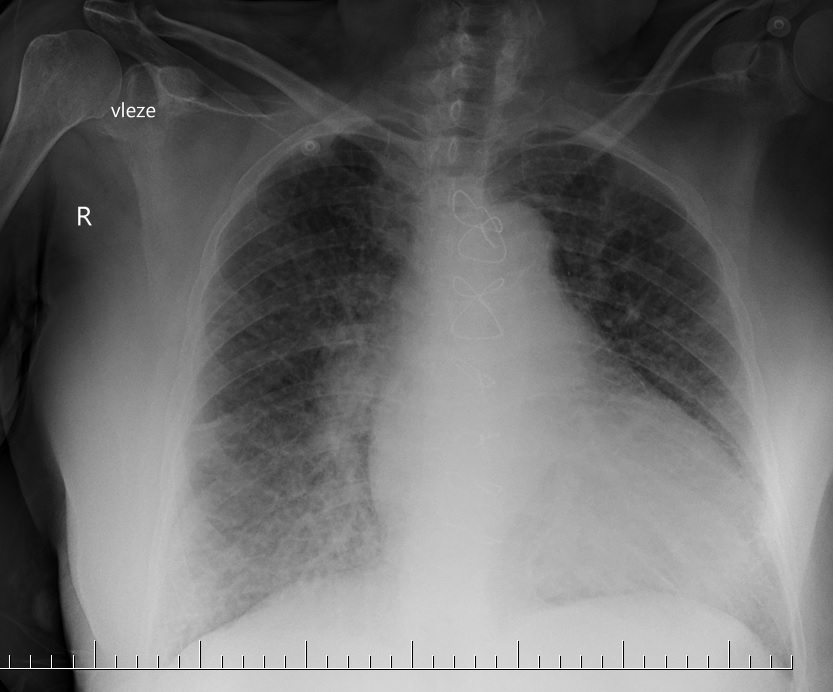

Jedná se o punkci perikardu za účelem evakuace perikardiální tekutiny (krev, výpotek, hnis) v situacích, kdy nahromadění tekutiny vedle k útlaku srdeční komory (zejména pravé) – srdeční tamponádě a hemodynamicky pak k příznakům obstrukčního šoku.

V nemocničních podmínkách se zpravidla provádí za ultrazvukové navigace. Zvyšuje se tak úspěšnost punkce a zároveň minimalizují případné komplikace výkonu. V terénu (přednemocniční péče) či při nedostupnosti ultrazvukového přístroje lze punktovat perikard tzv. naslepo, jen pomocí landmarks.